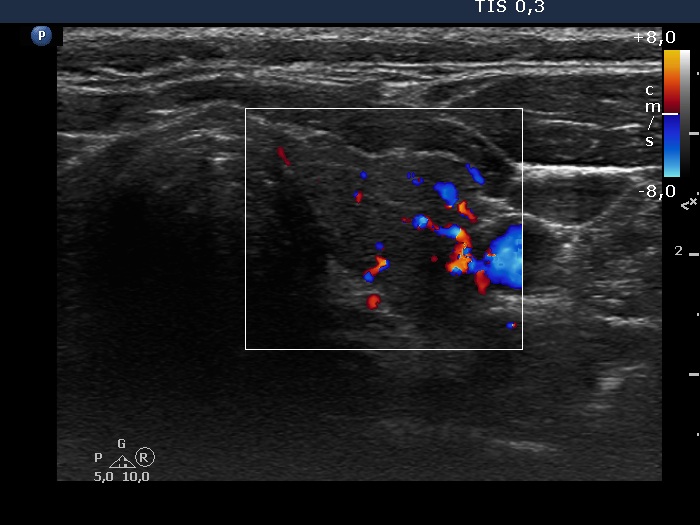

Consecutive patients with the final diagnosis of Hashimoto's thyroiditis - case 16 (509) (ultrasonographic picture 6)

Left lobe, transverse scan, color Doppler mode. The vascularization is a bit increased.